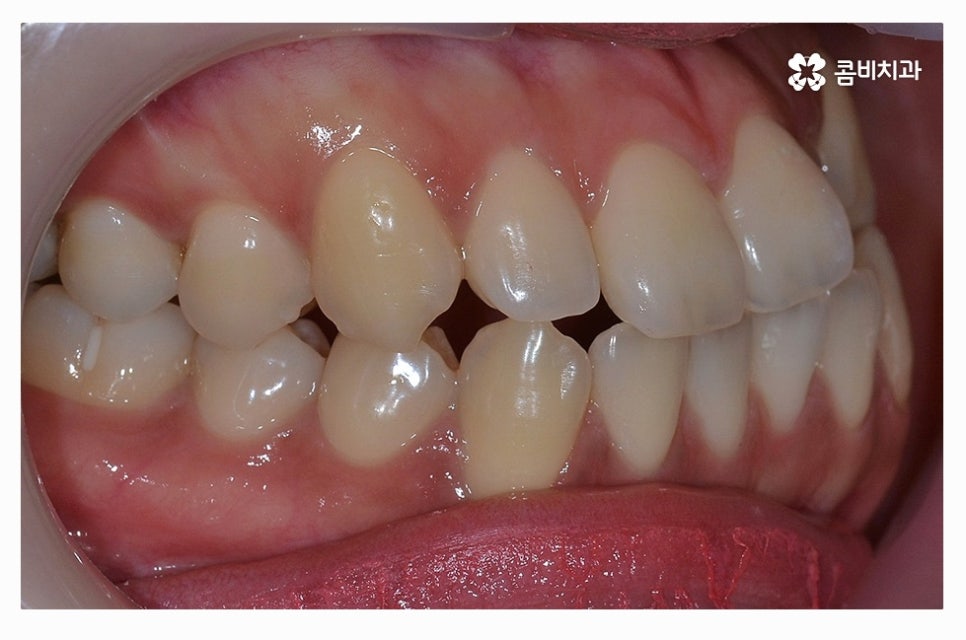

덧니교정은 치아의 이동 공간에 따라서 발치 혹은 비발치로

진행이 될 수 있는데 발치 여부는 골격, 돌출 여부, 치아의 이동 공간 확보 등에

따라서 개인차가 발생하며 치간 삭제나 악궁 확장과 같은 방법으로

비발치 교정을 하는 사례도 있어요.

발치 여부에 대해서는 정밀 검진을 통해서 의사와 상의해야 하며

무조건 비발치가 좋은 것이 아닌 심미성과 교합, 얼굴과의 조화 등을

종합적으로 파악하여 발치 여부를 정확하게 판단할 필요가 있어요.